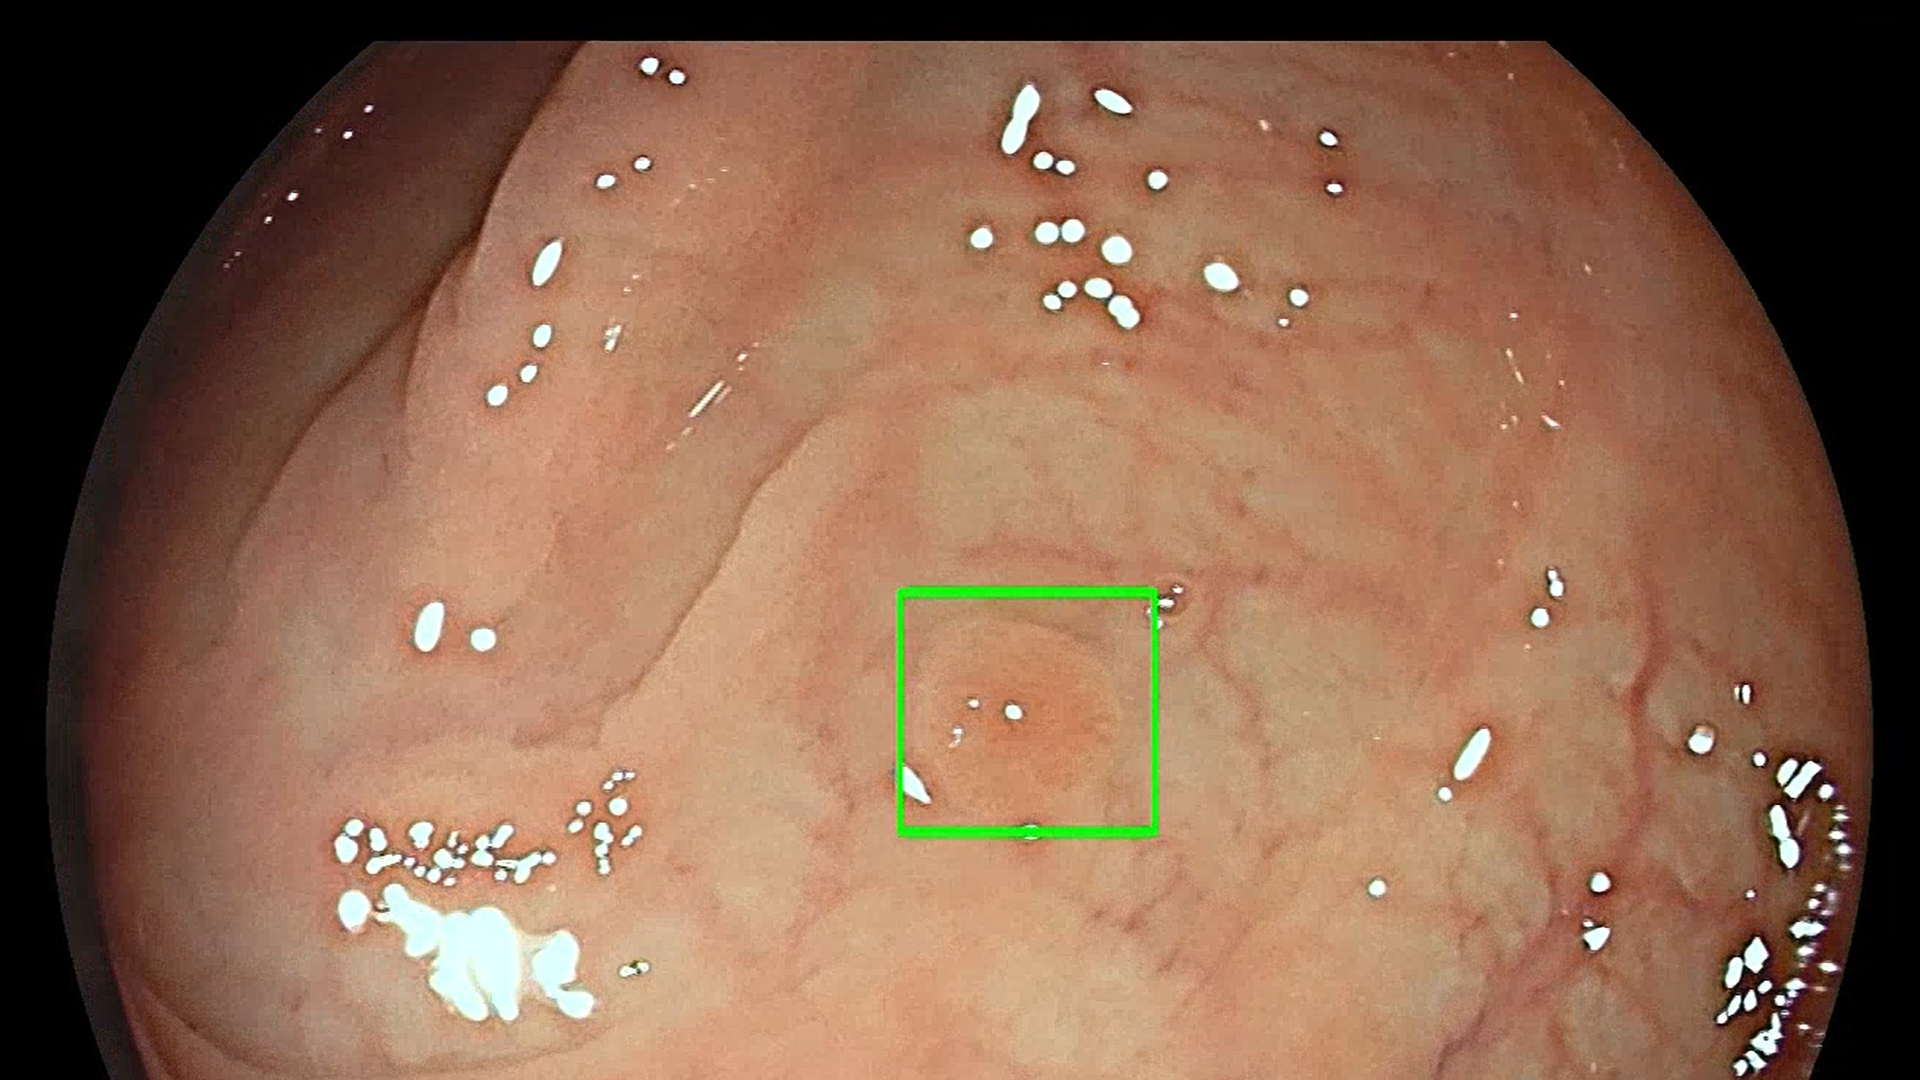

The GI Genius module uses advanced AI to highlight the presence of precancerous lesions with a visual marker in real-time – serving as an ever vigilant second observer. It processes images using advanced algorithms that can identify and mark abnormalities consistent with polyps, including small flat polyps that might otherwise go undetected by the human eye. Studies have shown that having a second observer can increase polyp detection rates and every 1% increase in adenoma detection rate (ADR) reduces the risk of colorectal cancer by 3%. Use of the GI Genius module has demonstrated a 14% absolute increase in ADR compared to colonoscopy alone for both flat (42% increase) and polyploid (36% increase) lesions, thus increasing accuracy and reducing the rise of interval cancers which can occur between colonoscopies.